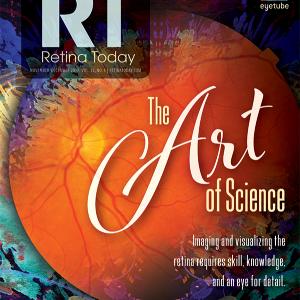

Intraoperative 4-D Microscope-Integrated OCT

This article originally appeared in the November/December Issue of Retina Today